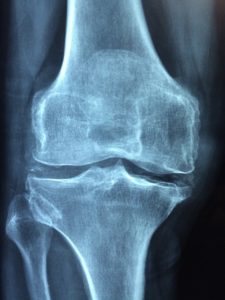

Røntgenundersøgelse